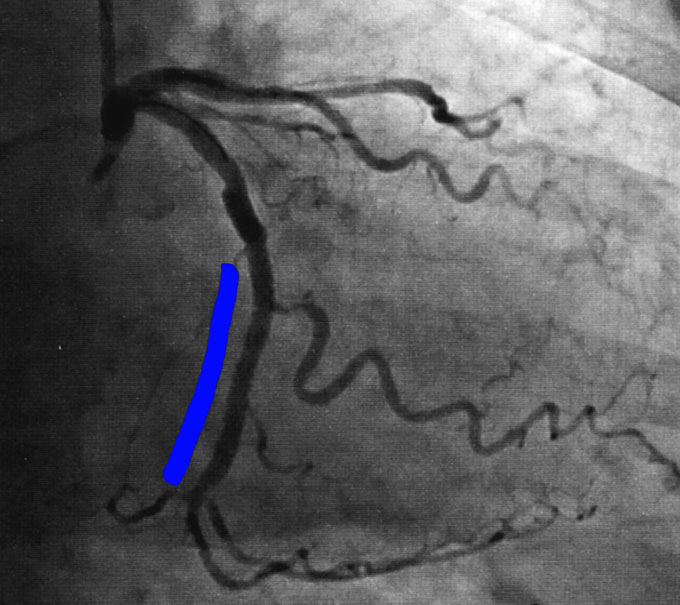

結局、さっき入れたステントのために、そこから枝分かれしている血管が詰まってしまって、血液が流れなくなっていたのですね(矢印)。確かに、造影剤が全く見えなくなっています。

そこからは、もうなんだか医療ドラマを見ているようでした。執刀医はこの枝にワイヤーを送って、なんとかそこにステントを入れようとしているのですが、それも、最初の手術と同じように血管の裂け目に入ってしまった可能性が強いのですね。彼は外に出てきて、まわりで見守っているたくさんの同業者の意見を聴いたりしています。その結果、裂け目をよけてもう一度ワイヤーを真ん中に通すことをトライすることになりました。その時には、この私が何とか成功させてほしいと「祈って」ましたね。こんなに真剣に祈ったことなど、初めてです。

祈りが通じたわけでもないのでしょうが、ステントは無事に留置出来たようでした。

この青いマーカーの脇が、ステントが入った部分です。はっきり血流が見えますね。結局、すべての手術が終わったのは午後1時、始まってから4時間半後でした。